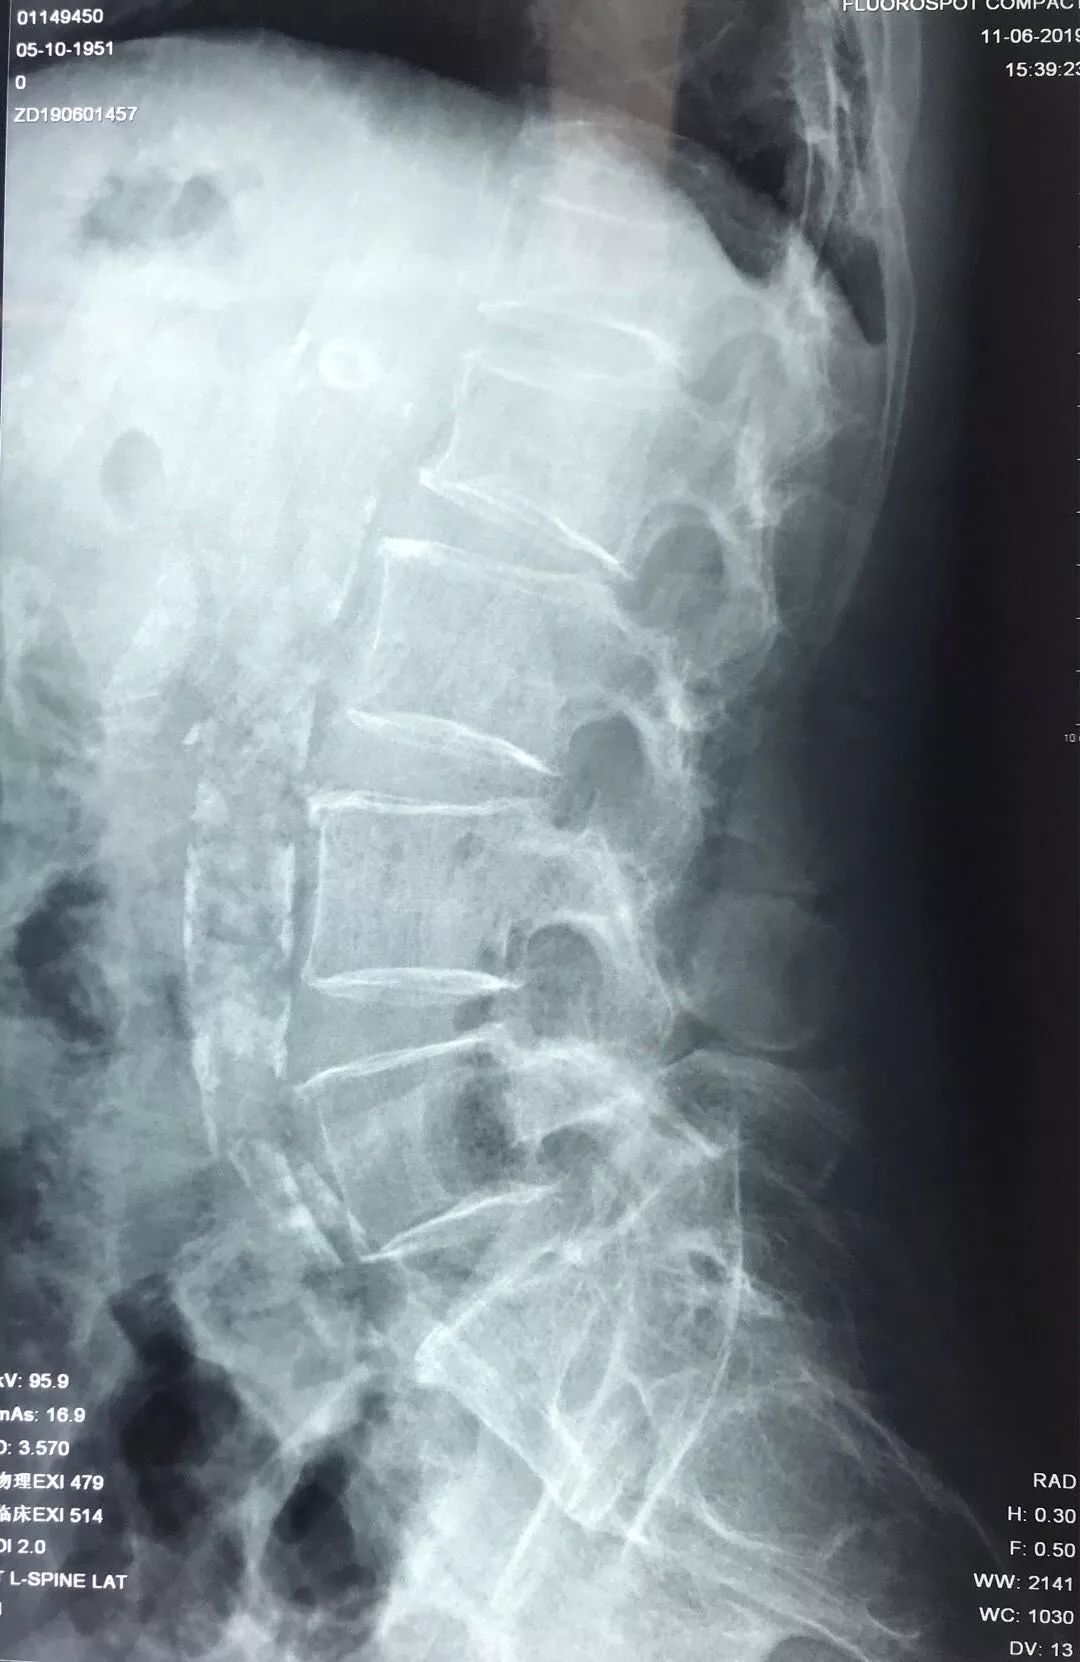

检查时发现,患者T12陈旧压缩性骨折,L1椎体新鲜骨折。但胸椎MR:T1加权象T1椎体呈弥漫性低密度改变,不同于一般椎体压缩性骨折的局限性水肿表现。

术前检查